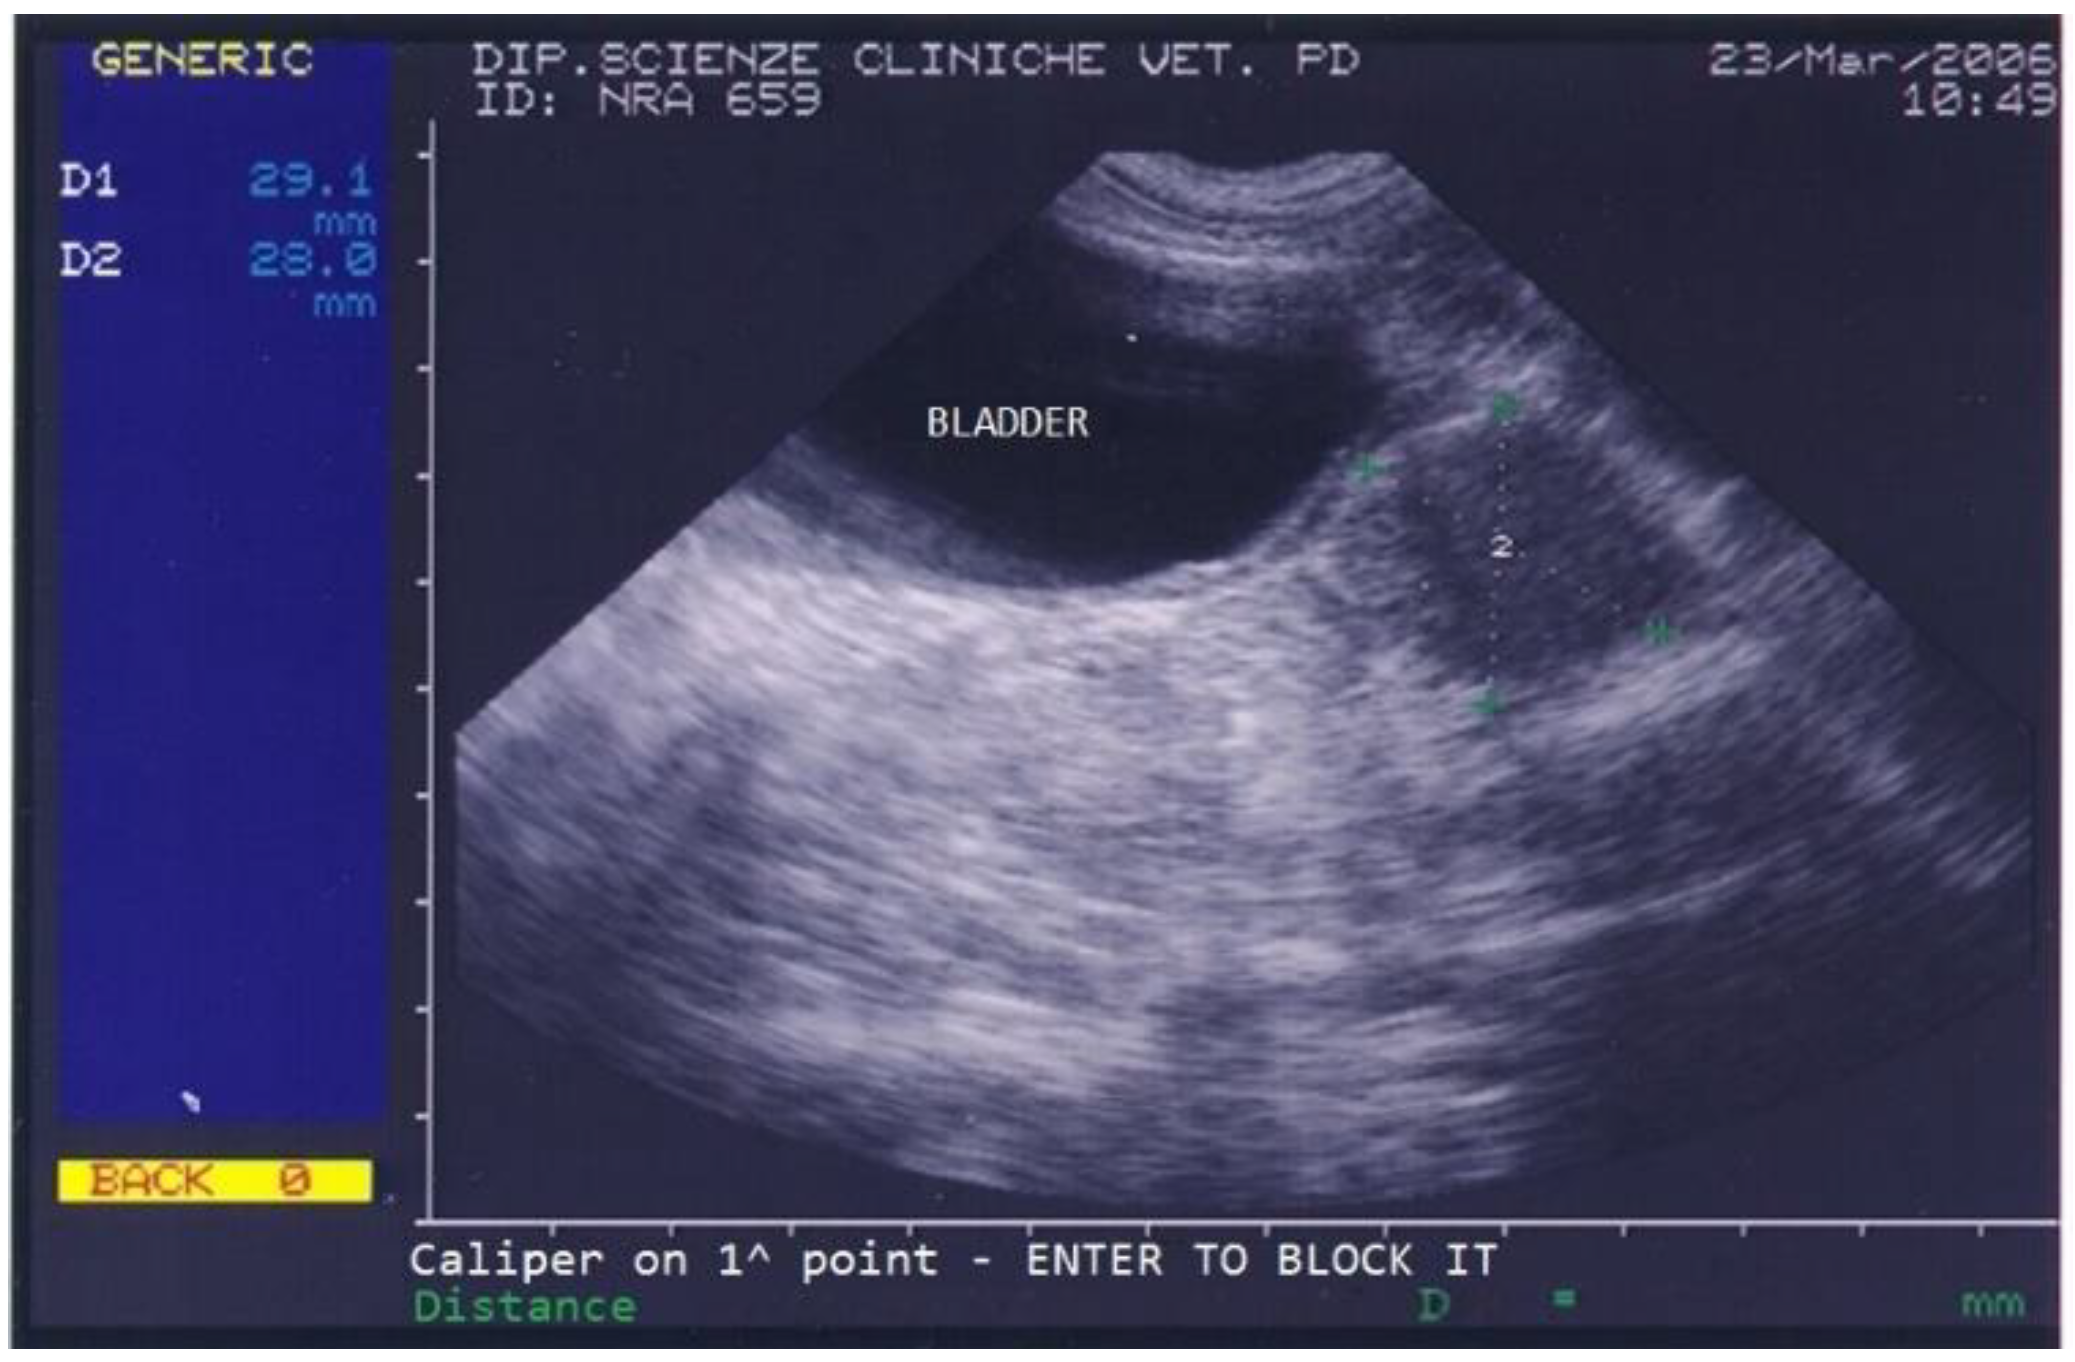

The dog returned for monthly follow-ups to monitor the implant’s action during the first 6 months, at which times a clinical exam, which included a prostatic ultrasound and a gonadotropin-releasing hormone (GnRH) stimulation test, was performed. The dog’s conditions improved remarkably already at the first monthly check when the dog showed no more difficult defecation and a normal appetite, and the ultrasound showed a progressive reduction in prostatic size and disappearance of all prostatic cysts. Upon reimplantation in March 2006, the dog’s prostate was very small (2.9 × 2.8 cm) and showed a normal texture (Figure 3).

Figure 3.

Abdominal ultrasonography of a German shepherd dog after a 4.7 mg deslorelin implant. The scan shows the ultrasonographic appearance of the bladder and prostate. The prostate’s perpendicular diameters are measured as D1 = 29.1 mm and D2 = 28 mm.